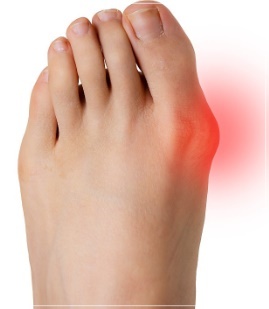

엄지 발가락의 튀어나온 관절부분(건막류)이 신발에 눌려 통증을 호소하는 것이 주 증상이나 엄지발가락이 둘째발가락 쪽으로 휘어져 있고, 관절이 안쪽으로 돌출되어 있습니다. 돌출된 관절은 서 있거나 걸을 때 자극을 받아 빨갛게 변하고 굳은살이 잡히며 염증과 통증이 발생합니다. 엄지발가락이 제 역할을 하지 못하니 발의 다른 부위에도 통증이 생기고 심해지면 발 모양의 변형, 허리의 통증 등이 발생합니다.